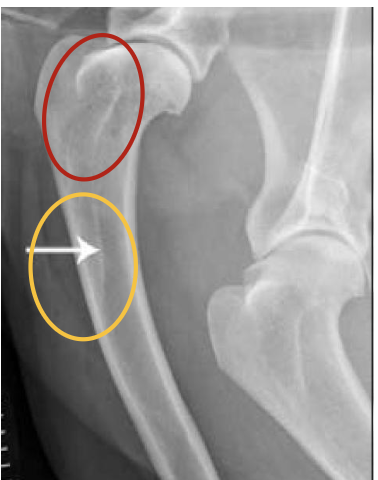

what are the orange circles showing?

mid-diaphyseal medullary region of the humerus (radioluscent)